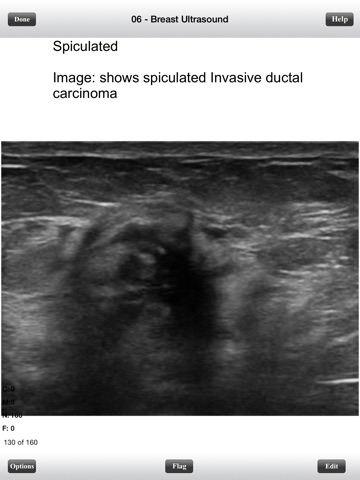

This is a fully functional version of ARDMS Ultrasound Breast Flashcards. It has only a few select cards for your evaluation. However, all options and features are active. This is the lite version for our ultrasound breast flashcard programs. The full version contains 1084 flashcards that will help you study and pass the ARDMS Breast boards. The program itself offers various features and options for a great and convenient learning environment which include: - Ability to Randomize cards - Can Flag cards for later use - Grade cards by using gestures - Study only missed cards, only new cards, only correct cards, flagged cards, or study all cards - Study all categories or selected categories - Timed mode to automatically flip card and advance cards. - Ability to edit and delete cards - Convenient statistics panel to see progress - Can change background color and text color - Can change text size - Can see back of card first Try it out!